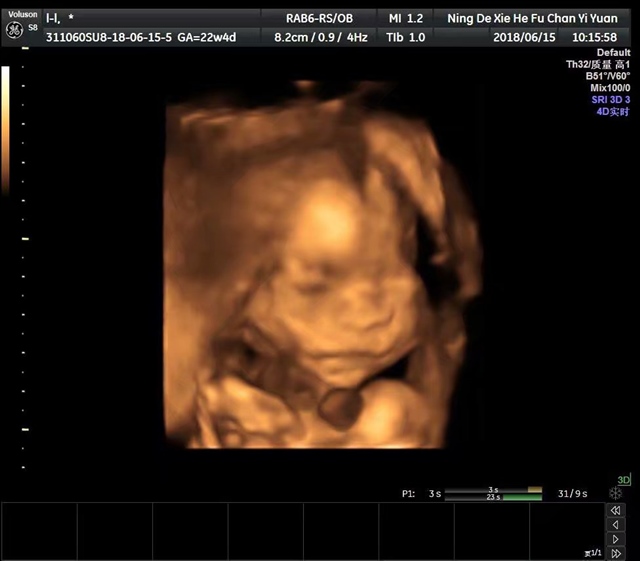

孕22周+3天

女宝么